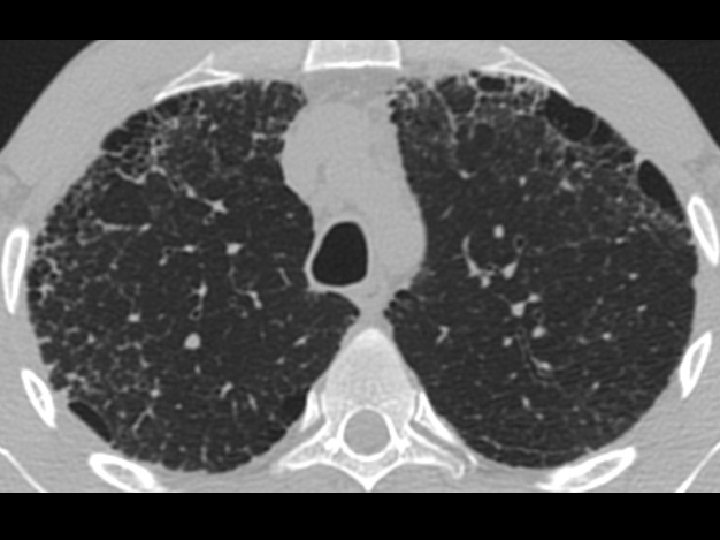

High-resolution CT scan

Subpleural, basal predominance Reticular abnormality Honeycombing with traction bronchiectasis UIPUIP Pattern

Subpleural, basal predominance Reticular abnormality Honeycombing with traction bronchiectasis Profuse micronodules UIPUIP Pattern Inconsistent with UIP Pattern